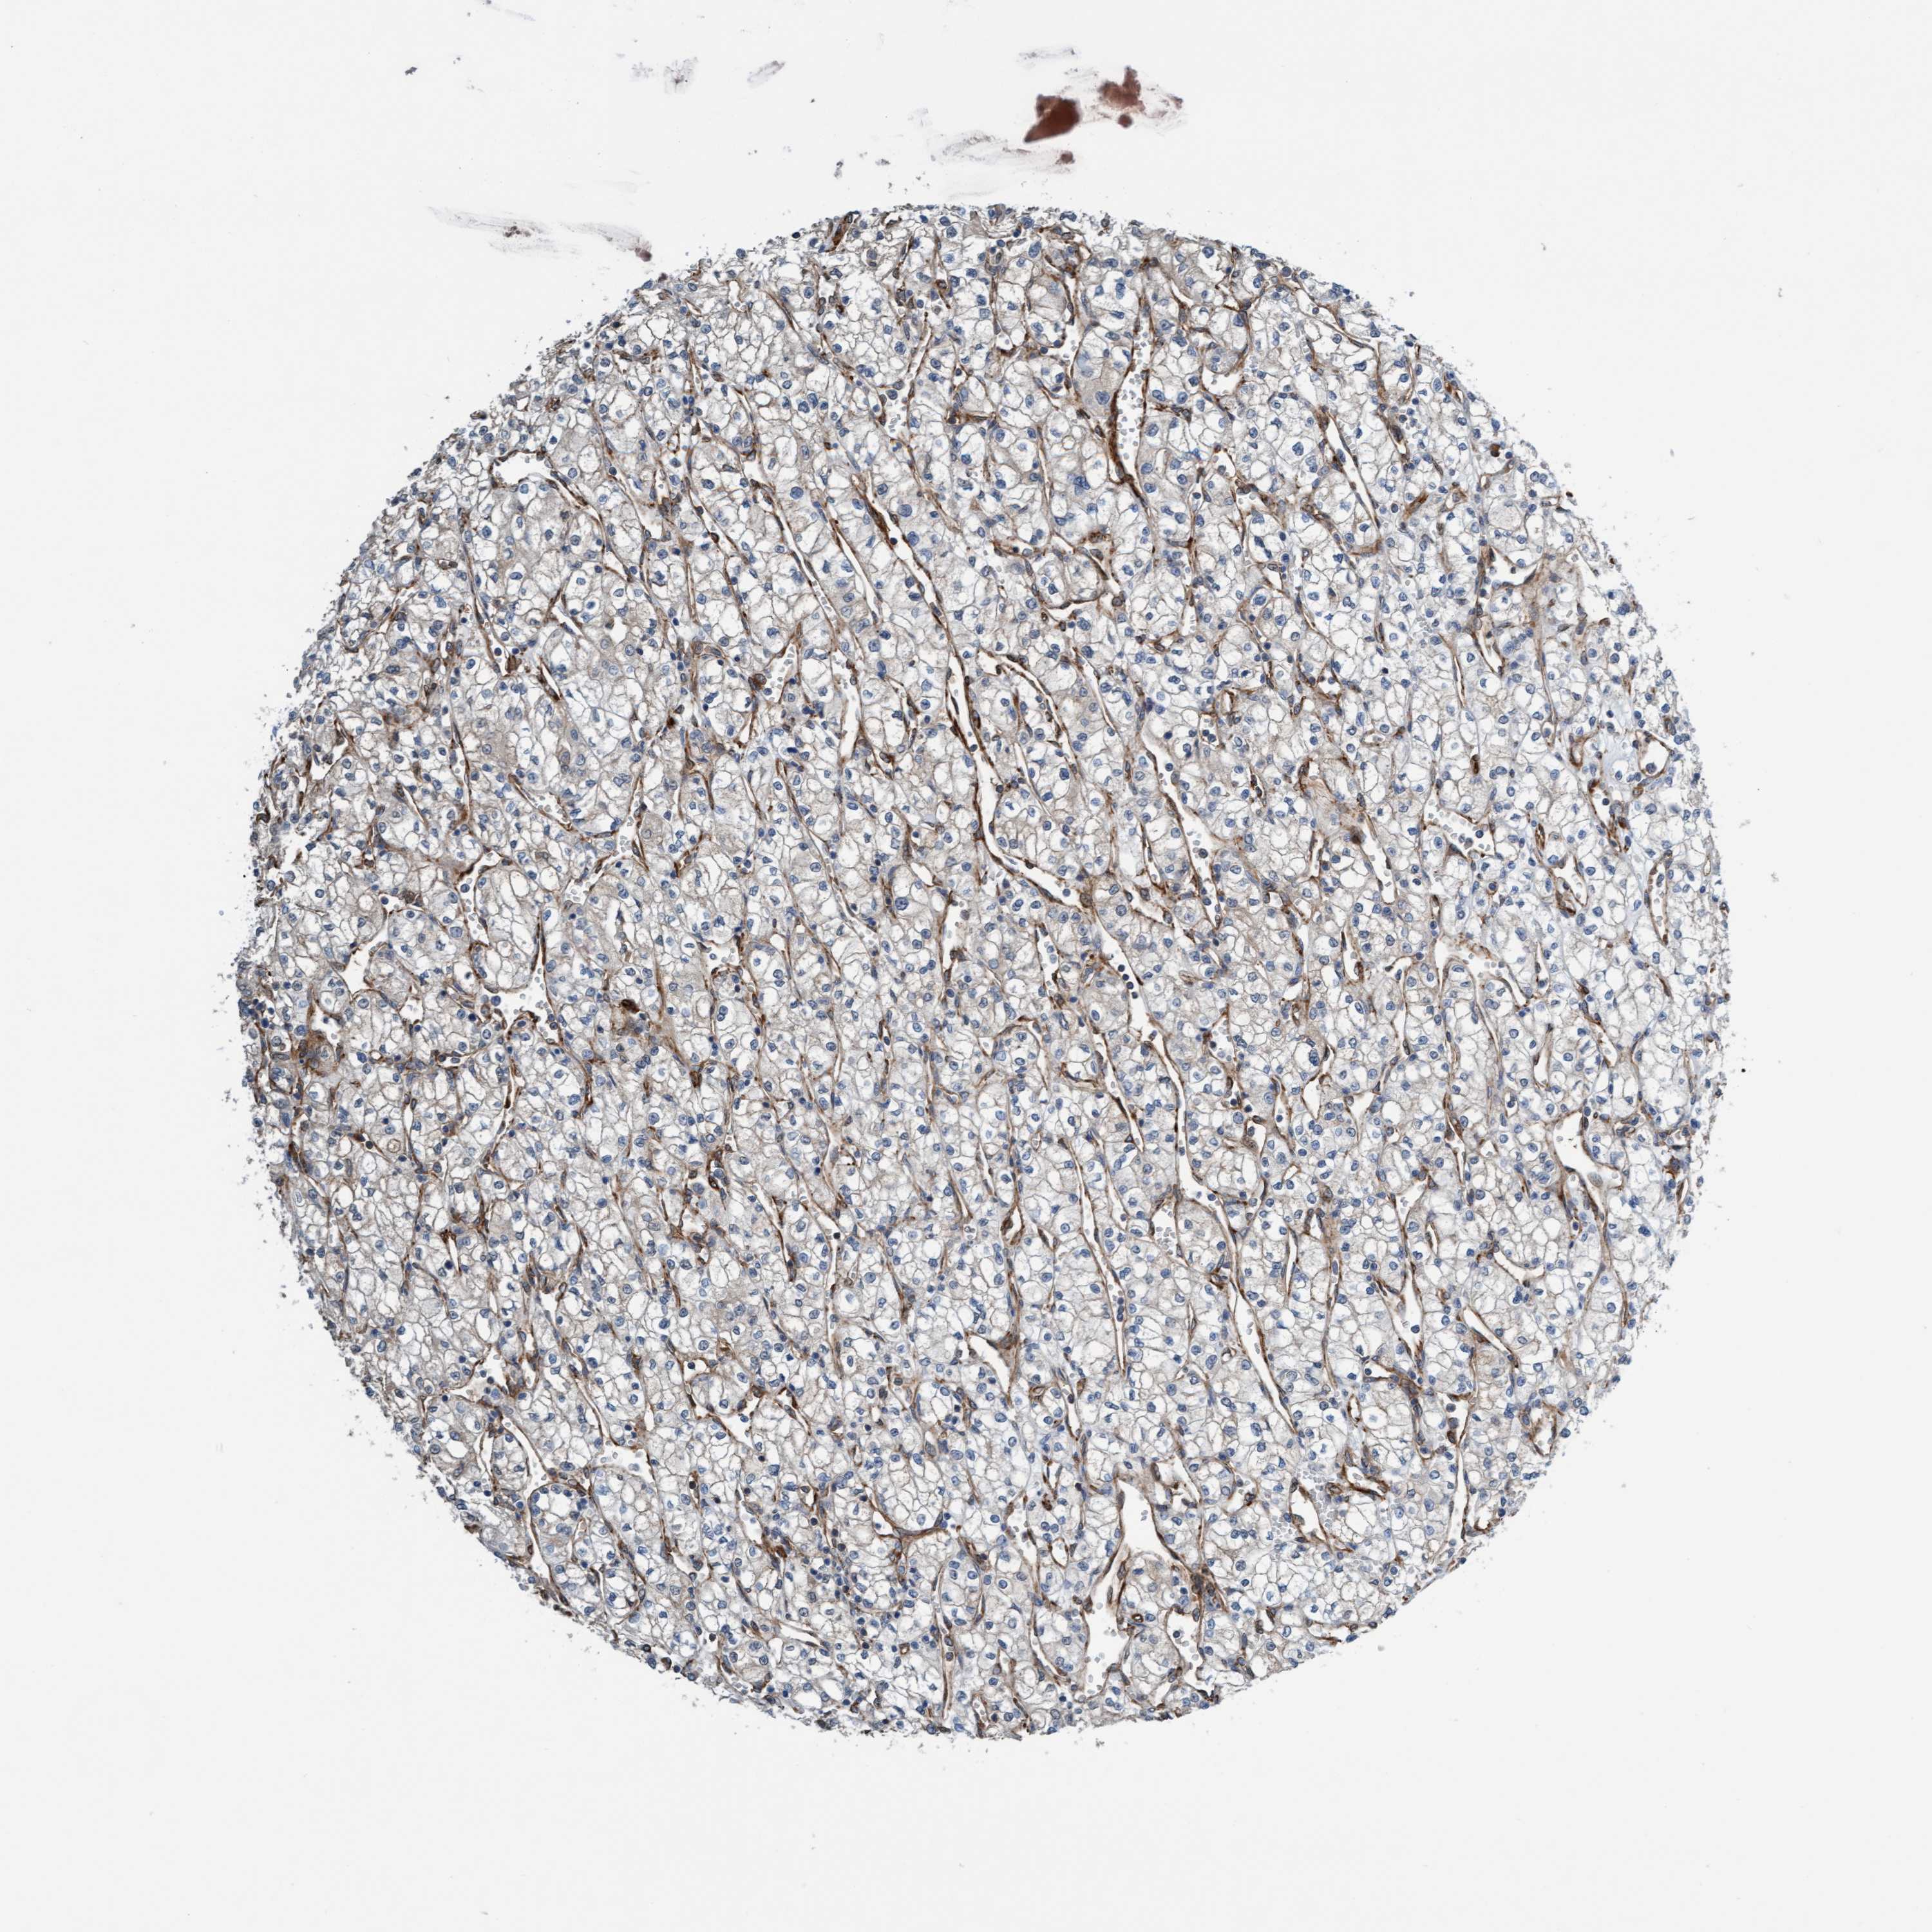

FMNL3 is not prognostic in Kidney Renal Papillary Cell Carcinoma (TCGA)

Best expression cut offi

Based on the FPKM value of each gene, patients were classified into two groups and association between prognosis (survival) and gene expression (FPKM) was examined. The best expression cut-off refers the FPKM value that yields maximal difference with regard to survival between the two groups at the lowest log-rank P-value. Best expression cut-off was selected based on survival analysis .

When clicking on this number, the vertical dashed line indicating cut-off, the interactive survival plot, and the Kaplan-Meier curve will be adjusted to show results based on the best expression cut-off.

: 3.1

Median expressioni

Median expression refers to the median FPKM value calculated based on the gene expression (FPKM) data from all patients in this dataset. When clicking on this number, the vertical dashed line indicating cut-off, the interactive survival plot, and the Kaplan-Meier curve will be adjusted to show results based on the median expression.

: N/A

Median follow up timei

Median follow up time refers to the median time (years) after diagnosis with this type of cancer, based on clinical data from all patients in this dataset.

P scorei

Log-rank P value for Kaplan-Meier plot showing results from analysis of correlation between mRNA expression level and patient survival.

N/A

5-year survival highi

5-year survival for patients with higher expression than the expression cutoff.

For melanoma and glioma, 3-year survival is shown.